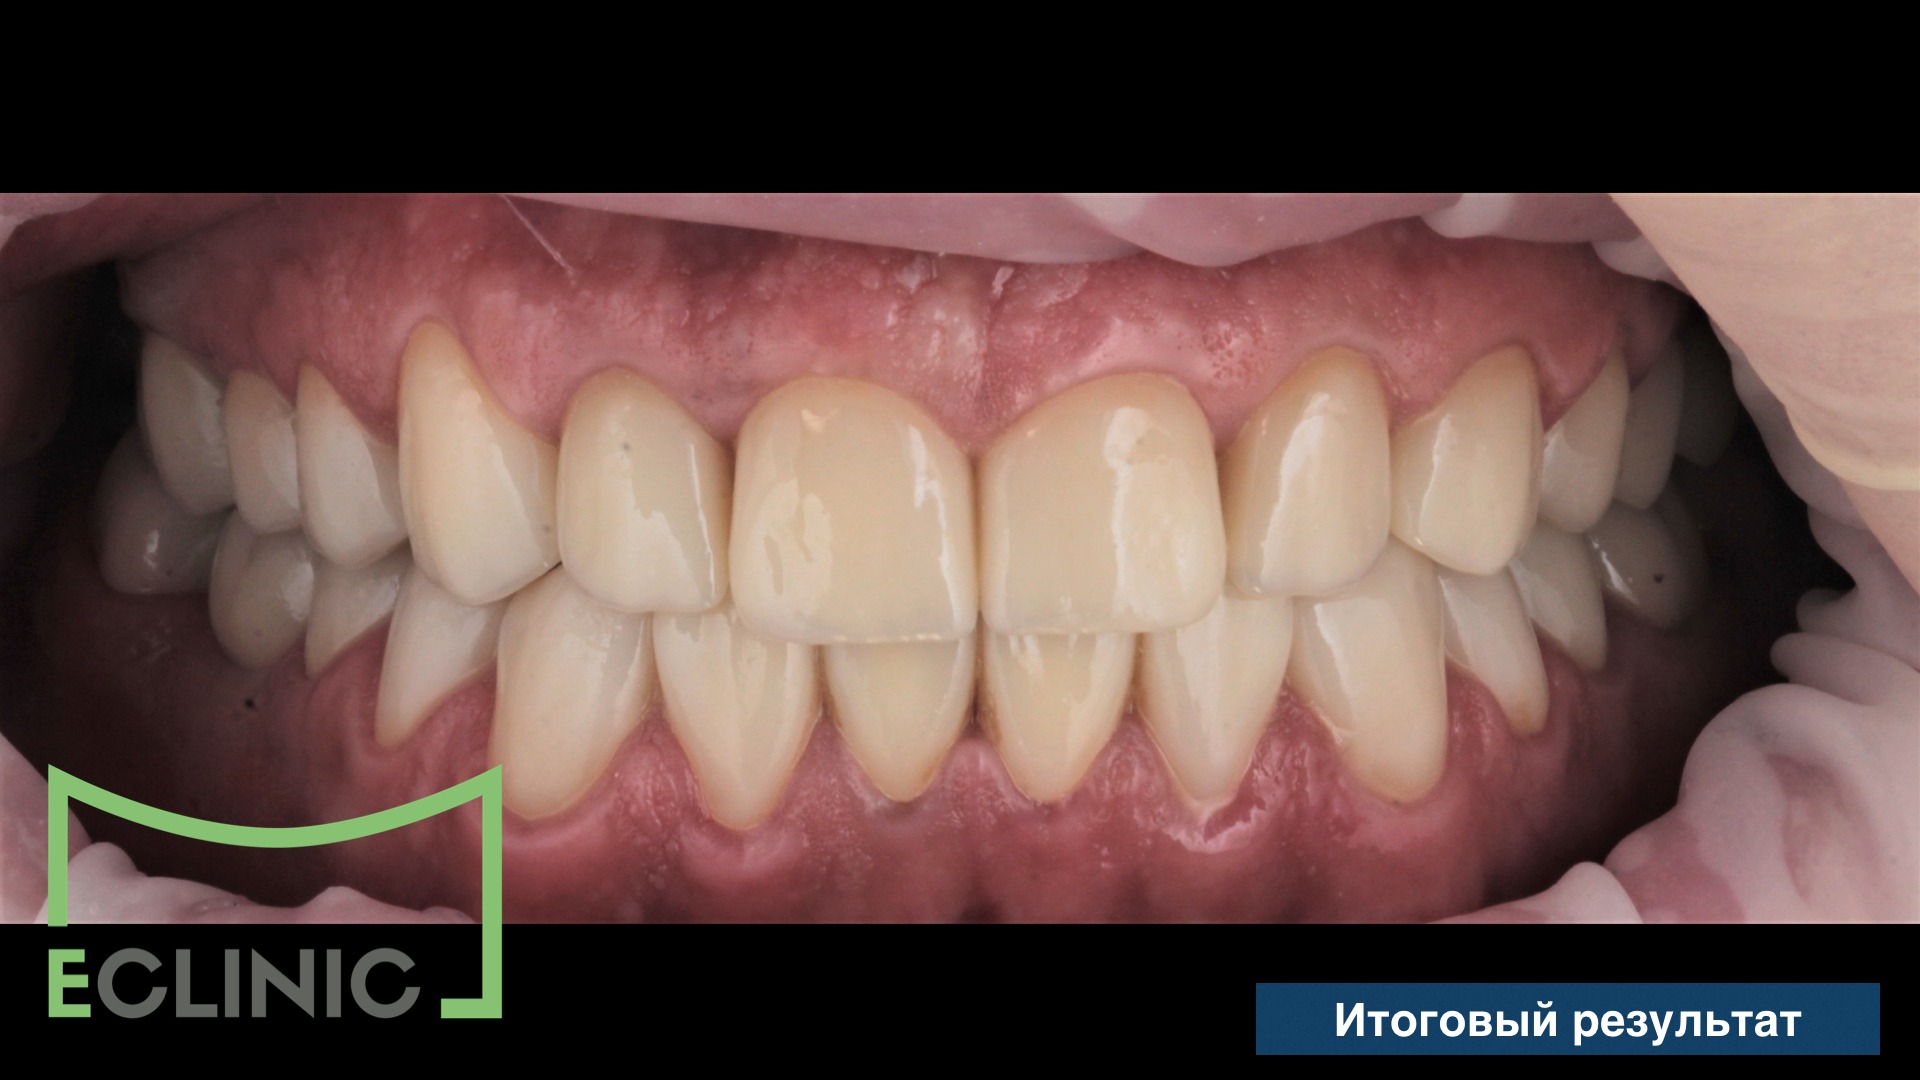

Нашим ортодонтом был собрана система для интрузии (внедрения) зуба 47 и, после 3 месяцев, мы завершили протезирование, установив две последние коронки.